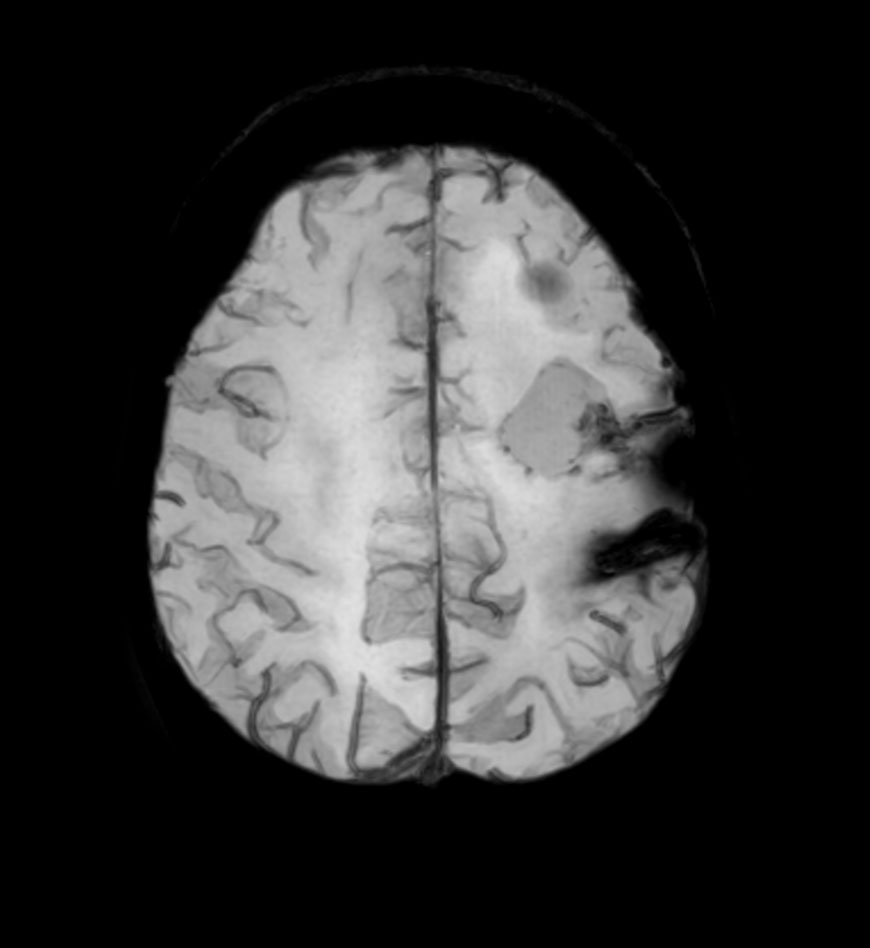

Axial DTI (b1000)

-

Axial DTI (ADC)

Axial DTI (FiberTrak)